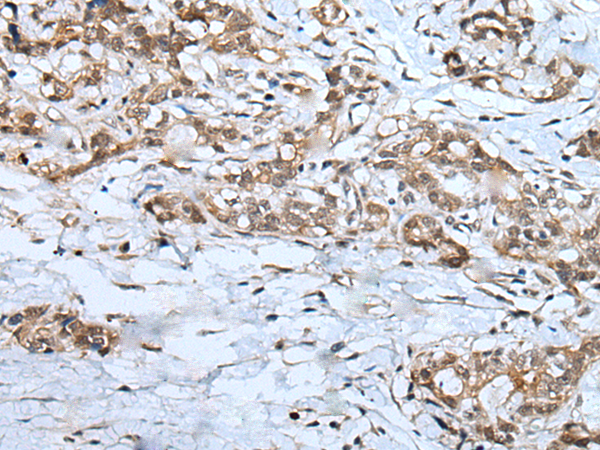

分类: 科研抗体货号: P09347别名: IRTKS应用: WB,IHC反应种属: Human, Mouse, Rat